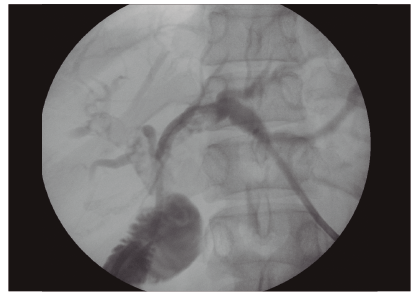

Se decide realizar el drenaje biliar de forma inmediata, teniendo en cuenta que se trataba de una paciente con colangitis severa. Debido al antecedente quirúrgico se optó por un acceso percutáneo. Se colocó por vía transhepática un drenaje interno-externo y se realizó una colangiografía donde se evidenciaron múltiples litos en ambas ramas hepáticas principales y en sus ramas secundarias. Asociado a esto, se observaba una estenosis de la hepático-yeyuno anastomosis (Figuras 1 y 2).

La paciente evolucionó de forma favorable con respecto al cuadro infeccioso, pero aún quedaba pendiente resolver el cuadro de litiasis compleja. Cuando las condiciones clínicas lo permitieron, se decidió aprovechar el drenaje que tenía colocado para realizar un drenaje endoscópico transpapilar percutáneo-asistido (rendez-vous) (Video WEB). Se pasó a través del drenaje percutáneo, bajo guía radiológica, una guía hidrofílica de vía biliar. Luego se ingresó con un colonoscopio de adultos al asa eferente hasta observar la guía. Se tomó la guía con un ansa y con su ayuda se logró avanzar hasta acceder a la hepático-yeyuno anastomosis. Se canuló la vía biliar con ayuda de la guía colocada en forma percutánea, y luego se progresó otra guía desde el colonoscopio. En primer lugar, se introdujo un balón de dilatación de 12 mm para dilatar la anastomosis, y luego se usaron una canastilla y un balón con los que se extrajeron, de forma completa, todos los litos de ambos hepáticos y sus ramas secundarias.